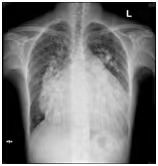

(图1)先天性心脏病患者(女,41岁)18F-FDG PET/CT显像图。1A.全身最大密度投影图示心脏明显扩大,房室各壁糖代谢明显增高;2B.心脏断层显像示各室壁糖代谢明显增高,SUVmax为11.5;1C.横断面、冠状面、矢状面三个不同层面示心腔明显增大,各室壁糖代谢明显增高。图2同一患者胸片。2A.2022年10月(手术前)胸片:心胸比为0.88;2B.2022年12月(手术后)胸片:心胸比例为0.76。